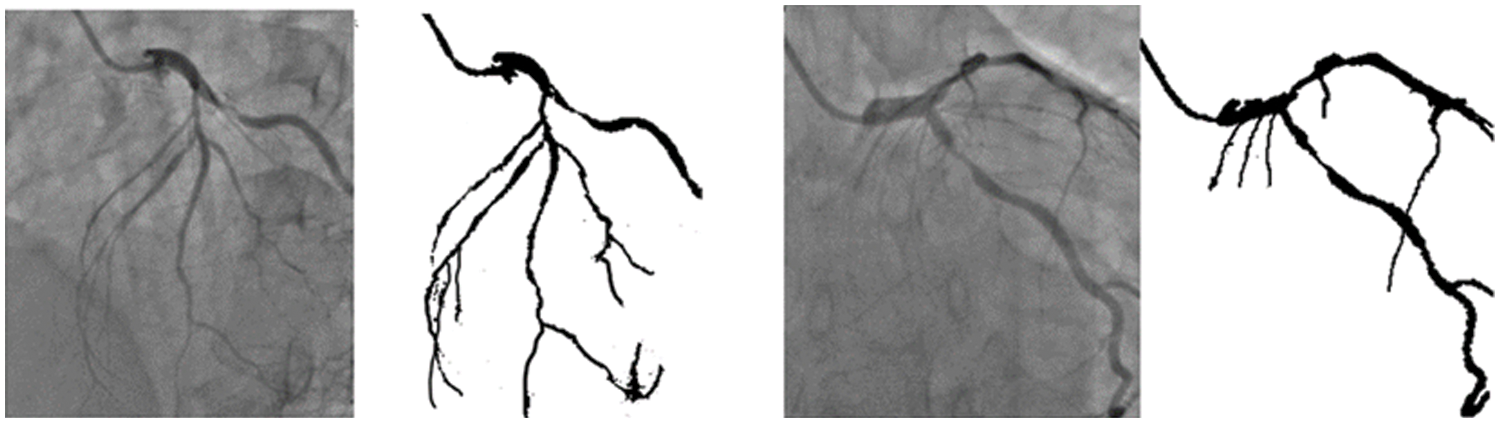

The training of the model is performed on a Tesla K80 GPU, compute 3.7, having 2496 CUDA cores and 12 GB GDDR5 VRAM in Google Collaboratory. The total RAM is 11 GB. Fig. 4 depicts the cloud training architecture of the model wherein some of the parameters are empirically chosen and the activation function used is ‘ReLU’. Fig. 5 provides the sample segment outputs for the corresponding input coronary angiograms. The images are inserted into the trained model and the output is the object for the input coronary angiogram image. The core python modules are placed in a Drive account and the Google Collaboratory is connected via Ocaml fuse socket. In this way, we make a line between data, code and runtime. With the help of the online free GPU, the training time reduces by a factor of 80 as compared to a normal CPU. The model is likewise trained online and stored in drive. The dice score achieved 94.

Figure 5: Sample segmentation outputs for the corresponding input angiograms